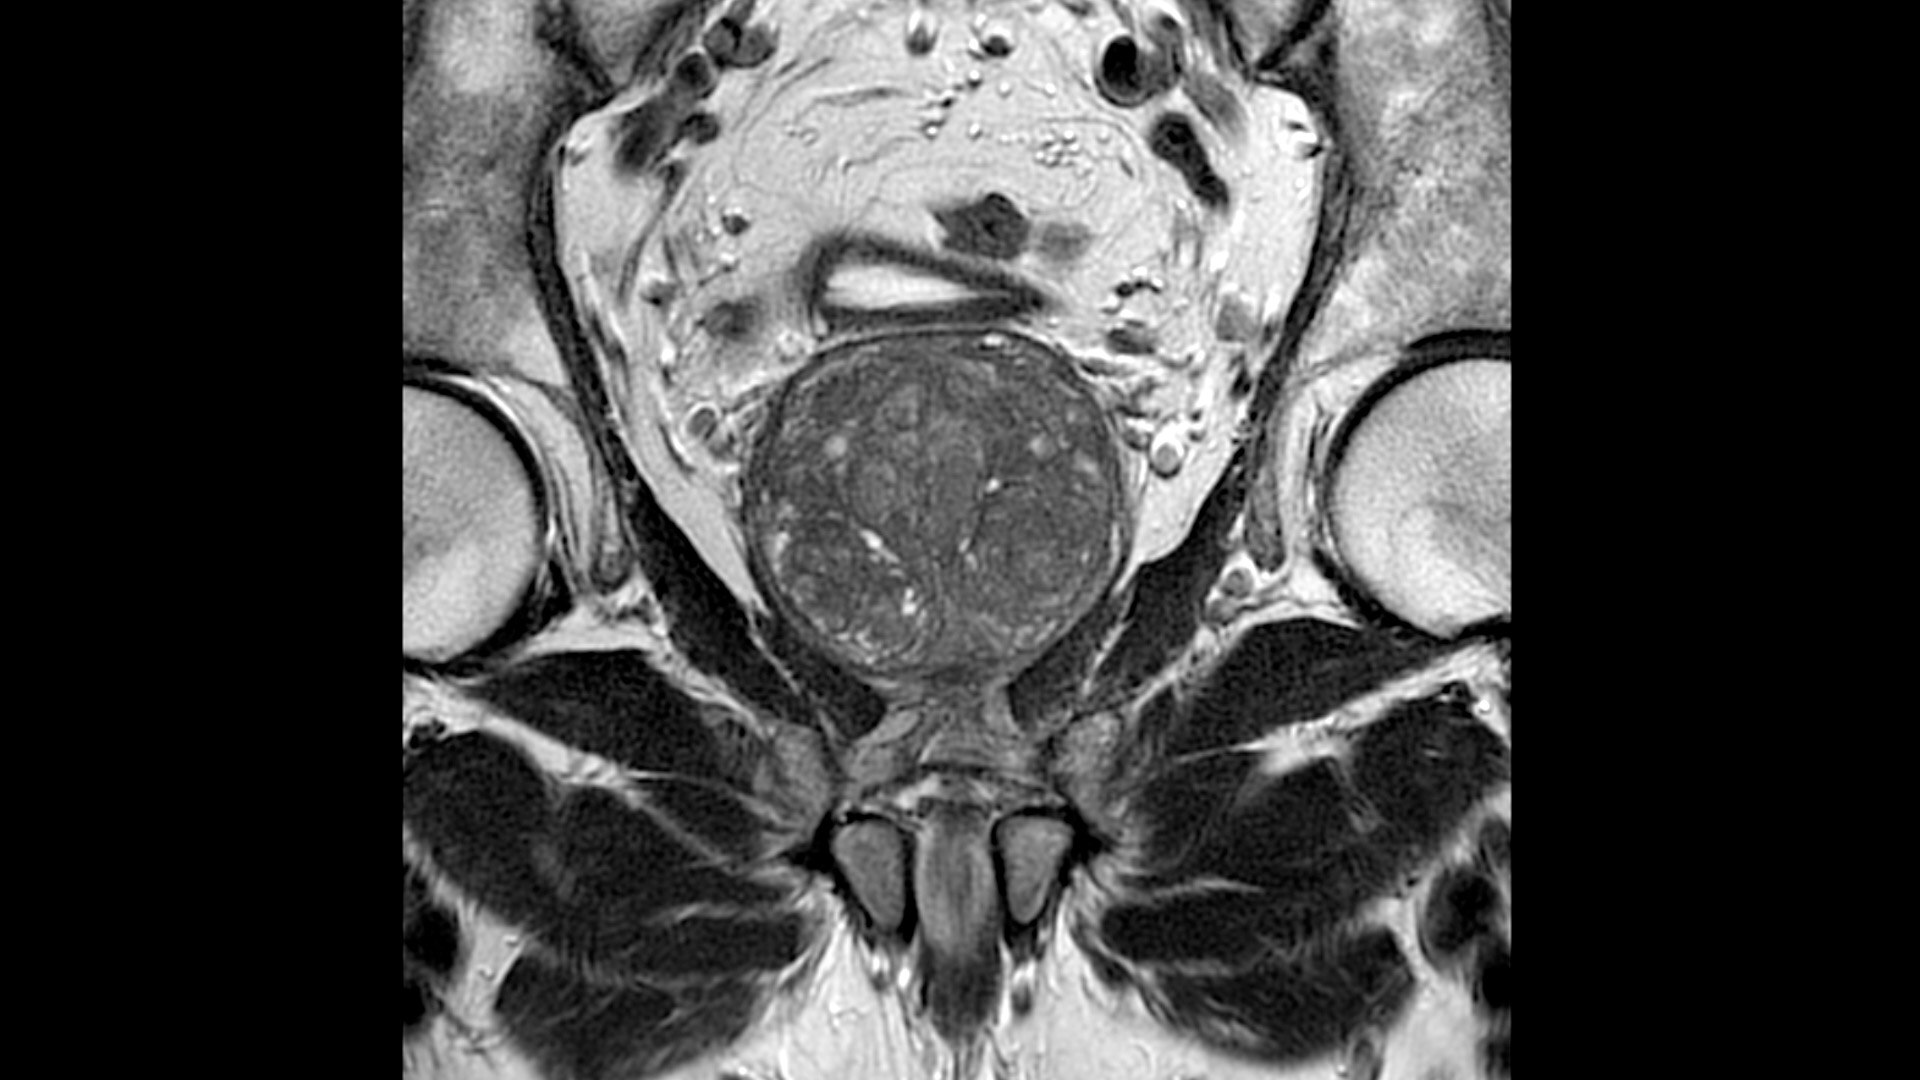

The shape of the MRI coil no longer determines what you can do with it. Wrap it around a knee for a complete knee image. Drape it over the patient's body. With an adaptive AIR™ Coil that is light, form fitting and easy to position, it’s the closest you can get to total positioning freedom with 360-degree coverage.

• 360 degrees of coverage for MSK imaging

• Positioning freedom with previously hard-to-scan anatomies

• 20-ch and 21-ch design to accommodate all patient sizes and anatomies